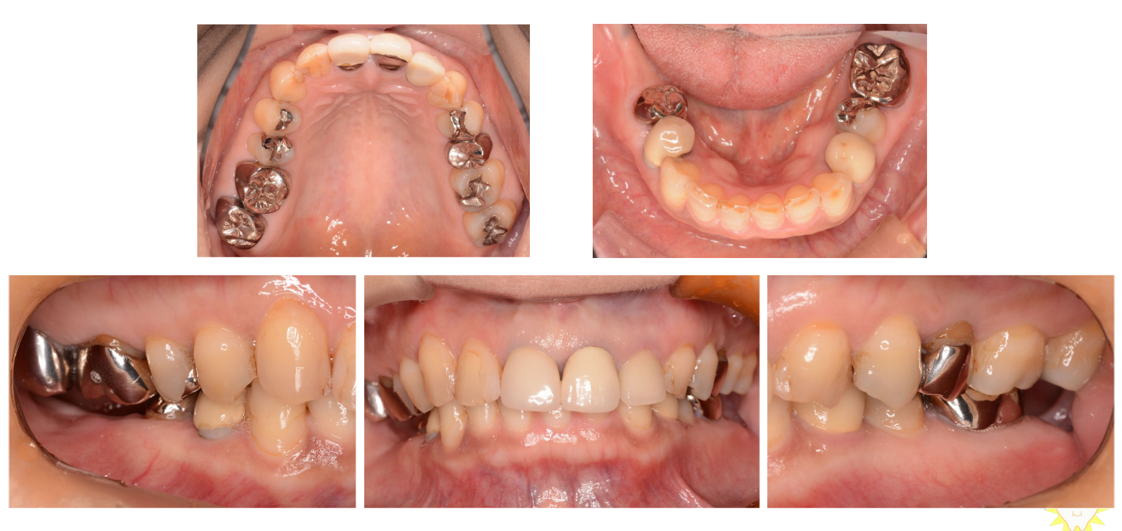

インプラント治療の症例1

(上顎の奥歯と前歯がない)

治療前

治療後

| 診断名・主訴 | ①右上インプラント希望 ②前歯と左上が痛い |

| 年齢 | 45歳 |

| 治療期間 | 2年間 |

| 治療内容 | インプラント治療 |

| 治療に用いた主な材料、設備機器 | 京セラFINESIAインプラント 上部構造:ジルコニアセラミック |

| 抜歯部位 | 左上1・6 |

| 治療費 | 約250万 |

| リスク・副作用 | 術後出血や腫れ |